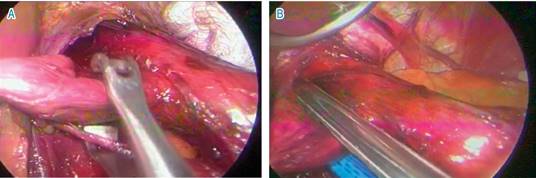

Una vez completado el protocolo, se decide llevar a cirugía, realizando un abordaje laparoscópico y transabdominal, colocando dos puertos de 10 mm, dos puertos de 5 mm y el separador hepático, como se usa de manera tradicional para funduplicatura, se inició disecando la pars flácida y, posteriormente, se disecaron vasos cortos, se creó una ventana retroesofágica y se colocó un Penrose 1/4 de pulgada para tracción, para así poder realizar una adecuada disección de los pilares diafragmáticos y del esófago; una vez disecado encontramos un divertículo posterolateral derecho a 3 cm de la unión gastroesofágica, el cual medía 3 × 3 cm, se disecan las adherencias al mismo y se separa el nervio vago, posteriormente se realiza corte con engrapadora lineal, EGIA cartucho morado y se procede a realizar cierre de los pilares diafragmáticos con punto en equis, con sutura prolene 2/0, se realizó funduplicatura laparoscópica tipo Nissen, colocando sonda de calibración número 40 French, con un tamaño de 5 cm y fijado con 3 puntos simples de prolene 2/0 y se da por terminado el procedimiento (Figura 4).

Figura 4: Cirugía. A) Se observa la disección del divertículo esofágico, ubicado en cara posterolateral derecha. B) Corte de divertículo con engrapadora lineal.